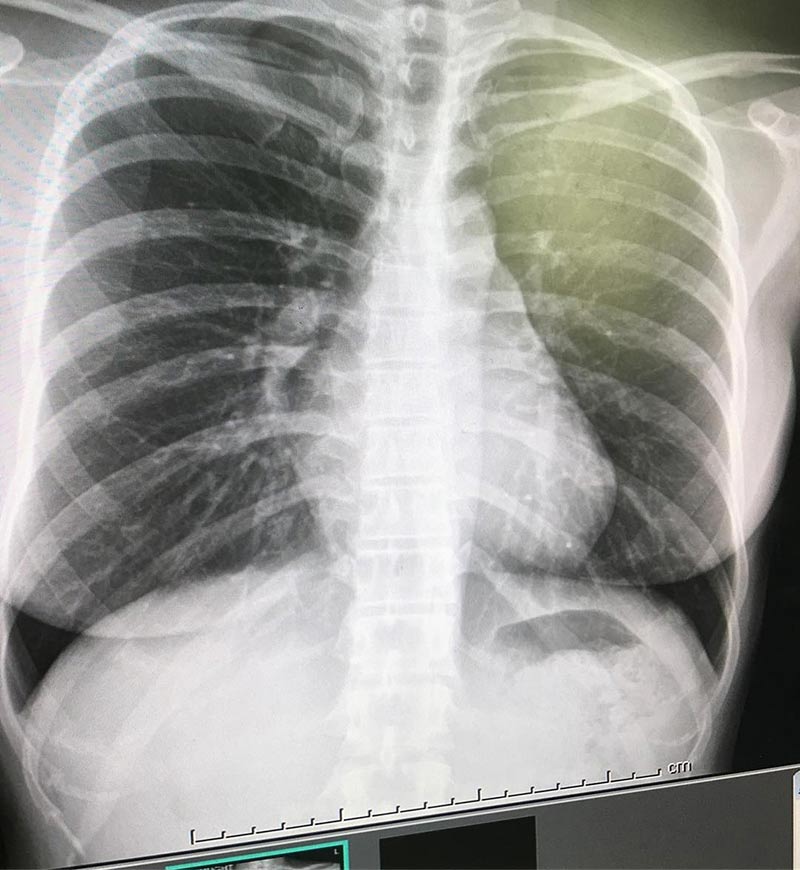

อย่างล่าสุด (25 เมษายน 2561) หนูเล็ก ก่อนบ่าย ก็ได้เผยถึงอุทาหรณ์สอนใจ เมื่อเจ้าตัวป่วยเป็นโรค โดยมีอาการไอหนักมาก และเมื่อไอก็จะเจ็บหน้าอก แต่ด้วยความฝังใจตั้งแต่เด็กว่าไม่ชอบกินยาเม็ดใหญ่ ๆ เลยไม่ยอมกินยา บวกกับคิดไปเองว่าเดี๋ยวโรคก็จะหายเอง แต่สุดท้ายแล้ว เมื่อไปเอกซเรย์ปอดกลับพบว่า ปอดของเธอนั้นแหว่งหายไป เพราะปล่อยให้ภูมิคุ้มกันสู้กับไวรัสโดยลำพัง

ทั้งนี้ หนูเล็กเองยังยืนยันว่า ตอนนี้ตนเองยังทำงานได้ แต่ต้องกินยาฆ่าเชื้อ และฝากถึงทุกคนด้วยว่า อย่าเข้าใจผิดคิดว่าโรคจะหายไปเองได้ เพราะอย่างตน หมอเองยังชมเลยว่า ไวรัสลงลึกขนาดนี้ แต่ยังทำงานได้ทุกวัน